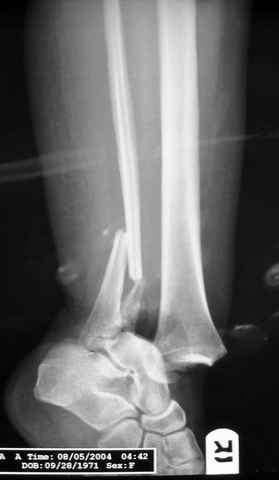

Re: ANKLE FRACTURE

Второй случай сделан из одного разреза

На прямой проекции послеоперационного Рг макроскопически все выглядит очень анатомично, при микроскопическом ( :-)) ) рассмотрении можно все-таки заметить вальгизацию тарана, суставная щель в латеральном отделе сустава несколько уже , чем в медиальном при отсутствии латерального смещения тарана. У меня был аналогичный случай (без LISS , без мини доступа) с вальгусным наклоном тарана при восстановленном ankle mortise при последовательном наблюдении с интервалами в 6-8 недель в послеоперационном периоде отмечалось прогрессирующее сужение суставной щели в латеральном отделе сустава, закончившееся посттравматическим ОА, к счастью боли умеренные, купируемые аналгетиками или своими эндорфинами:-))(активная пациентка, у которой нет времени на болезни....) Какова жизненная ситуация в приведенном вами случае? И последнее, что я хотел бы прояснить для себя - фиксация внутренней лодыжки: я обычно комбинирую фиксацию компрессирующим винтом со спицей - по идее ротационная стабильность должна быть лучше, чем один винт, каковы ваши наблюдения в этом плане?